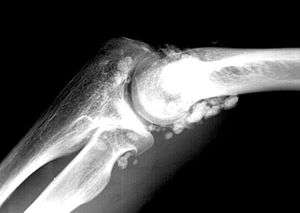

| X-ray of an elbow affected by synovial chondromatosis | |

Synovial chondromatosis (synonyms include synovial osteochondromatosis, primary synovial osteochondromatosis, and synovial chondrometaplasia) is a disease affecting the synovium, a thin flexible membrane around a joint. It is also known as Reichel's syndrome or Reichel-Jones-Henderson syndrome, named after Friedrich Paul Reichel, Hugh Toland Jones and Melvin Starkey Henderson.[1]

In the early stages of the disease it is often confused with tendinitis and/or arthritis. Once it reaches transitional the loose bodies become apparent with X-ray in greater than 70% of cases, with MRI often showing where xray fails. In experienced hands, US is also useful for the diagnosis.[2]

In the disease, the thin flexible membrane of the synovium gradually forms blisters which calcify and enlarge. These nodules eventually break free and float around the joint space becoming larger – these add to the discomfort and stiffness of the joint.

The disease generally affects only one of the larger weight bearing joints (hip, ankle, knee) – although the elbow, and wrist can also be affected. Rarely involves the temporal mandibular joint.[3]